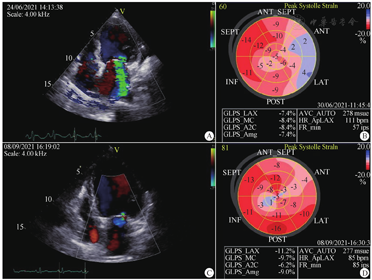

)等针对冠状动脉痉挛的治疗后症状无改善,心肌酶持续升高。监测NT-proBNP较前明显升高,考虑心力衰竭加重,先后予西地兰、地高辛,静脉硝酸甘油、呋塞米等治疗以及多巴胺维持血压,患者仍反复胸痛、喘憋发作,换用小剂量左西孟旦0.1 μg·kg-1·min-1无效。风湿免疫科会诊考虑目前无免疫病、原发血管炎证据。心电图ST段持续抬高,外院两次冠状动脉造影显示无固定狭窄,冠状动脉痉挛或缺血性心脏病均不能解释当前临床表现,心肌酶持续升高,也不符合典型扩张型心肌病表现,考虑诊断为免疫介导的炎症所致心肌病可能性大。因常规治疗后患者症状仍持续加重,考虑心肌存在炎症损伤坏死,6月30日加用静脉甲强龙60 mg/d×3 d,继之40 mg×3 d后换口服泼尼松龙50 mg/d。治疗后患者症状明显改善,肌酸激酶、肌酸激酶同工酶逐渐正常,cTnI降至5 μg/L;逐步减停多巴胺。心力衰竭稳定后加用美托洛尔3.125 mg每日2次。免疫科随诊认为糖皮质激素治疗有效,考虑免疫或炎性因素参与发病,建议激素逐步减量,加用复方环磷酰胺每日1片。出院时患者无不适主诉,可下地缓慢行走。出院后泼尼松龙逐渐减至35 mg/d,继续复方环磷酰胺每日1片,美托洛尔3.125 mg每日2次,达格列净等治疗。9月8日患者门诊复诊,诉未再有胸痛发作,夜间能平卧,可简单干家务,血压90/60 mmHg,心率78次/min。因血压偏低,暂未加用血管紧张素转换酶抑制剂/血管紧张素Ⅱ受体拮抗剂类药物。复查多项免疫指标均阴性,cTnI 0.081 μg/L,NT-proBNP 10 071 pg/ml,血沉降至8 mm/第1小时,高敏C反应蛋白降至3.12 mg/L,复查超声心动图示房室大小无明显变化,LVEF 37%,肺动脉压正常,二尖瓣反流及反映左室收缩功能的左室纵向应变较前明显改善(图6C、图6D)。

A:病初心尖四腔心切面显示大量二尖瓣反流;B:病初左室纵向应变异常;C:治疗2个月后心尖四腔心切面显示少量二尖瓣反流;D:治疗2个月后左室纵向应变改善